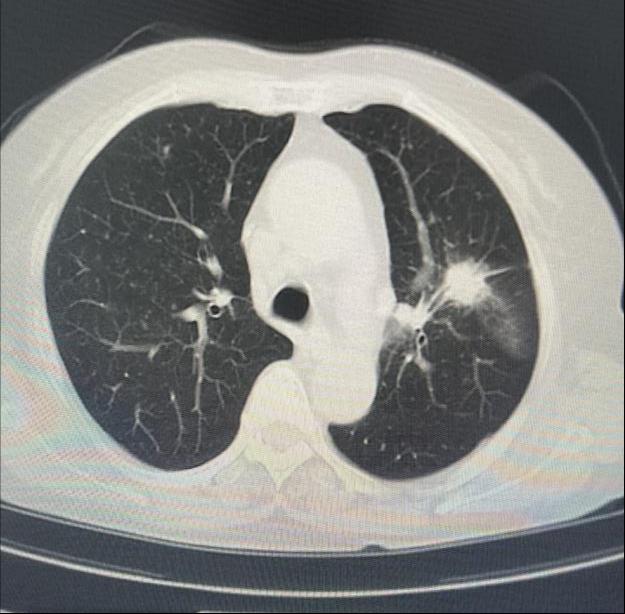

患者女性,因“气短1月”来门诊就诊,为明确诊断进一步治疗,收入乐鱼在线登录入口。入院后完善相关检查,胸部CT示左肺上叶前段高密度灶,与家属充分沟通后,决定为患者行超声支气管镜检查。主任医师吴水淼与主管护师薛冬冬为患者行气管镜检查,镜下示:双肺支气管均未见明显异常,结合CT给予超声探查,于左肺上叶前段亚支探及偏心异常回声区,由于亚支位置较高且管腔较窄,活检钳无法到达,给予冷冻肺活检。此次检查过程顺利,成功获取2块活检标本,活检病理结果提示为粘液腺癌。